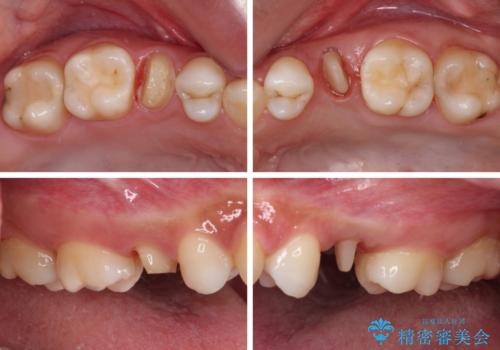

- 根管治療が必要な虫歯を放置した結果、抜歯が必要と診断されたとのことで来院された患者様です。

口腔内の状態やレントゲン写真から判断し、長期的なことを考えると抜歯が無難と思われましたが、それを承知の上で保存するための処置を行うこととしました。

まずは虫歯を除去した上で根管治療を行い、部分矯正により骨内深い位置にまで及んだ健全な部分を引っ張り出すこととしました。

かなり深い位置にまで虫歯が及んでいたため、かなりの量を引っ張り出す必要があり、残された歯根は短く小さい状態となりました。

今後も定期的にレントゲンを撮るなど、経過を追っていく必要があります。